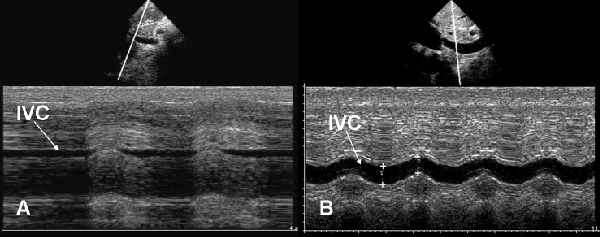

| Figure 5: Abdominal longitudinal scan of inferior vena cava. A. M-mode of inferior vena cava (IVC) in a hypovolemic patient: IVC is slight and completely collapse during inspiration. B. M-mode of IVC in a patient with high central venous pressure: IVC is large with minimal changes of diameter during inspiration. |